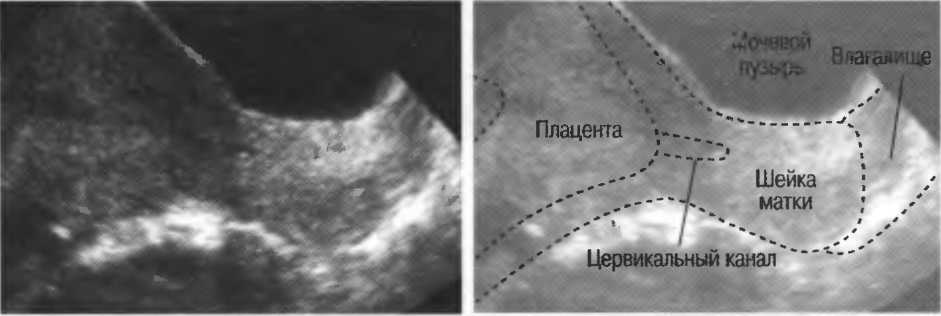

Реверберации могут полностью менять изображение, создавая линейные структуры или зеркальное отображение. Например, реверберации между параллельными слоями подкожных тканей создают параллельные линейные структуры в мочевом пузыре (рис. 20в).

Рис.20в. При сканировании матки через наполненный мочевой пузырь параллельные датчику слои тканей передней брюшной стенки могут вызывать появление ревербераций, которые определяются как зхоструктуры в передних отделах мочевого пузыря на фоне анэхогенной полости. Поперечный срез (слева) отличается от продольного среза (справа) при изменении положения датчика.